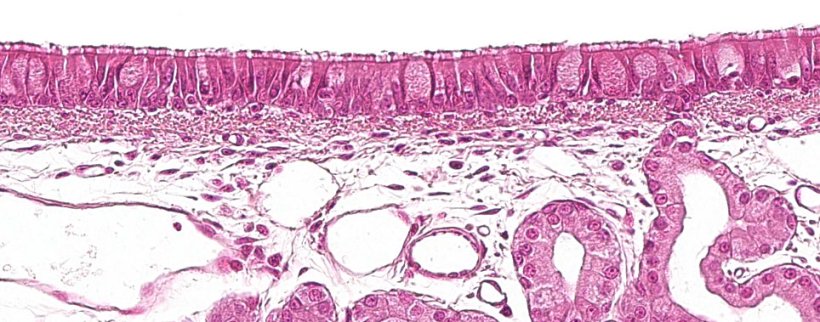

La première partie du système respiratoire, la partie conductrice ou voies respiratoires, va de la cavité nasale aux dernières branches des bronchioles, et comprend également les sinus nasaux et paranasaux qui sont connectés à la cavité nasale, au nasopharynx et au larynx. Toutes ces structures tubulaires sont revêtues par un épithélium cilié pseudostratifié avec des cellules caliciformes (figure 1), responsable de l'un des principaux systèmes de défense de la muqueuse respiratoire, l'appareil mucociliaire. Ce système est composé des cils des cellules de l'épithélium respiratoire, ainsi que des sécrétions des cellules caliciformes et des glandes séromuqueuses qui apparaissent sous la muqueuse respiratoire et sa fonction principale est d'éliminer les particules qui pénètrent par l'air inspiré. Les glandes sécrètent un liquide clair, de faible viscosité et riche en protéines qui est disposé entre les cils, formant un milieu qui favorise leur mouvement vers le haut. Le mucus sécrété par les cellules caliciformes se dépose sur les cils et permet l'adhérence des particules inhalées. Le mouvement ascendant des cils pousse le mucus vers la partie supérieure du système respiratoire; celui-ci peut être avalé et passer dans le système digestif, où il est digéré, ou expulsé à l'extérieur par la bouche et / ou la cavité nasale. Des agents tels que Mycoplasma hyopneumoniae qui provoque la perte de cils, ou des virus tels que la grippe porcine ou le coronavirus respiratoire qui provoquent la destruction des cellules épithéliales exercent leur action pathogène en détruisant ce système défensif.

Figure 1: Épithélium pseudostratifié cilié avec des cellules caliciformes caractéristiques du système respiratoire.